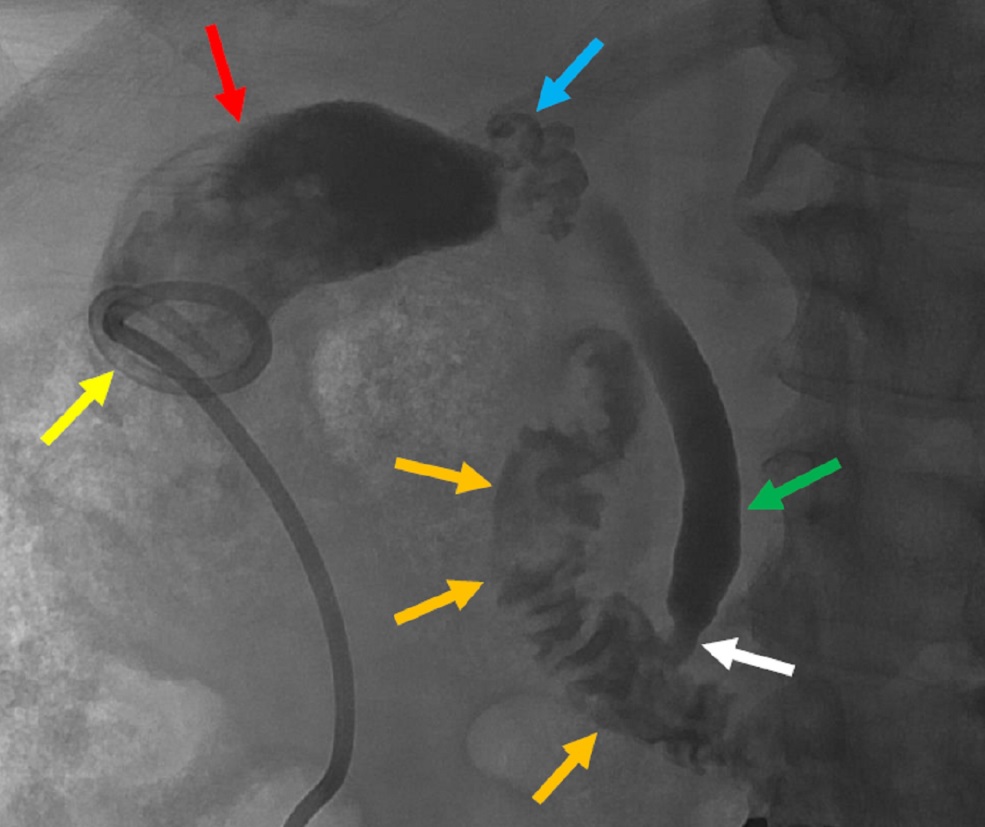

담관은 간에서 십이지장으로 연결되는 관 네트워크로, 담즙을 운반하여 지방의 소화와 흡수를 돕고, 폐쇄 시 황달을 유발하며, 담관 배액 시술 등으로 치료한다. - 염증 - 신장염

우상 복부 사분원 초음파 검사는 담낭염을 진단하는 데 가장 일반적으로 사용된다.[4][26][27] 급성 담낭염을 시사하는 초음파 소견에는 담석, 담낭 주위 액체(담낭 주변의 액체), 담낭벽 비후(벽 두께 3mm 이상),[28] 담관 확장 및 초음파 머피 징후가 있다.[13]초음파 검사에서 담낭염의 특징적인 소견은 초음파 머피 징후(초음파 프로브로 담낭 압박에 의한 통증), 담낭벽 비후(>4mm), 담낭 종대(장축경>8cm, 단축경>4cm), 멈춘 담낭 결석, 데브리 에코, 담낭 주위 액체 저류, 담낭벽 sonolucent layer, 불규칙한 다층 구조를 나타내는 저에코대, 도플러 신호이다.

CT 스캔은 천공이나 괴사와 같은 합병증이 의심되는 경우에 사용될수 있다.[14] CT에서 담낭염의 특징적인 소견은 담낭벽 비후, 담낭 주위 액체 저류, 담낭 종대, 담낭 주위 지방 조직 내 선상 고흡수역 등이다.

MRI에서는 담낭 결석, pericholecystic high signal, 담낭 종대, 담낭벽 비후 등을 확인할 수 있다.

민감도가 더 높은 간 이미노디아세트산 (HIDA) 스캔은 초음파 검사가 진단적이지 않은 경우 사용할 수 있다.[13][14]